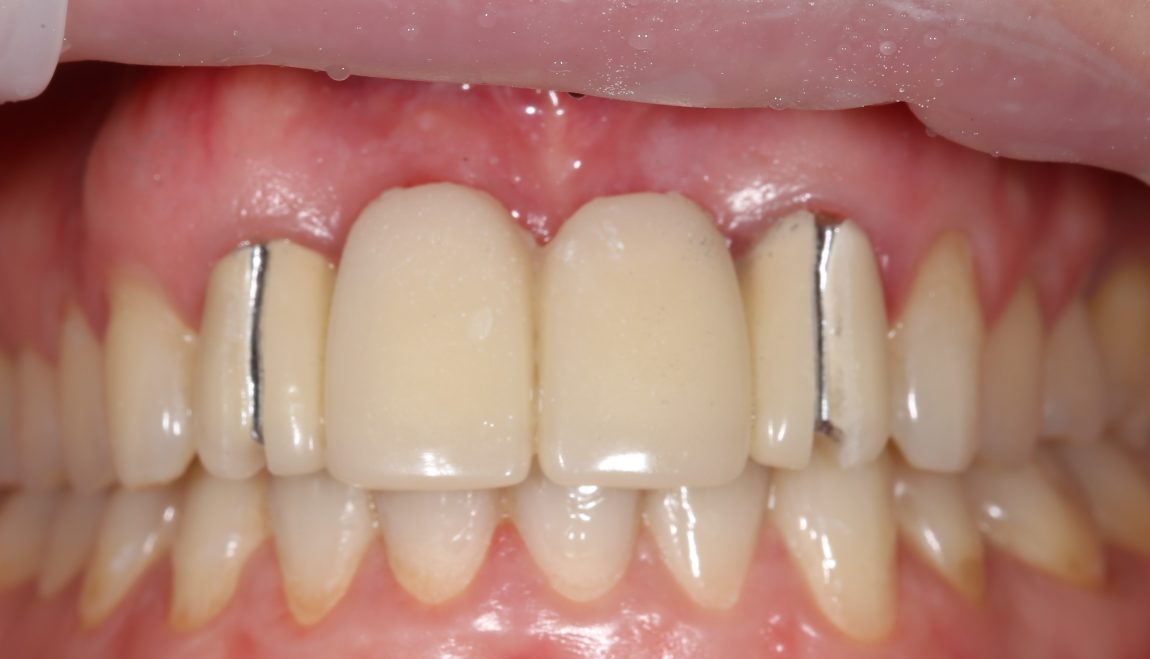

Вместо реплантаций (что легко) и реставраций (что сложнее), её тогдашний стоматолог решил решил депульпировать и обточить два боковых резца и сделать мостовидный протез. С тех пор прошло много времени, протез несколько раз меняли, а зубы перелечивали. На момент обращения к нам, верхние резцы у Татьяны выглядели следующим образом:

Пациентку беспокоили дискомфорт в области протеза, небольшая подвижность и периодическое воспаление десны в области опорных зубов.